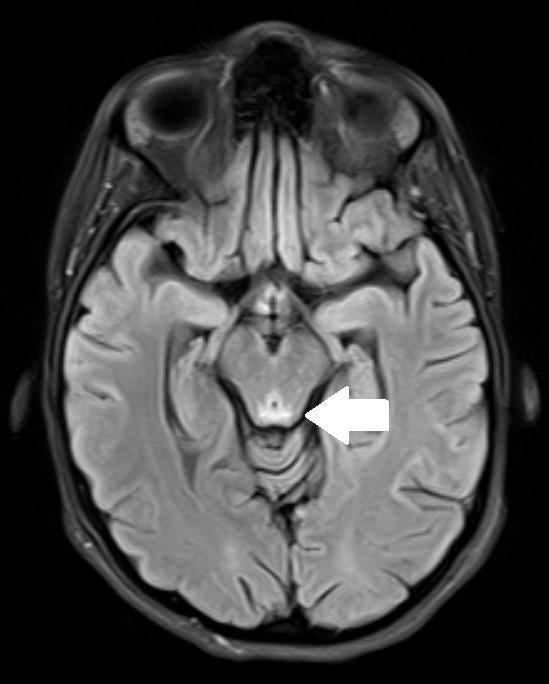

349 Acute Cerebellar Infarct in A Patient with Undiagnosed Fahr’s Syndrome: A Case Report

RW Slaven, M Huecker, D Kersting

377 Undiagnosed Schizencephaly Presenting as Breakthrough Seizures

J Coacci, P Viccellio